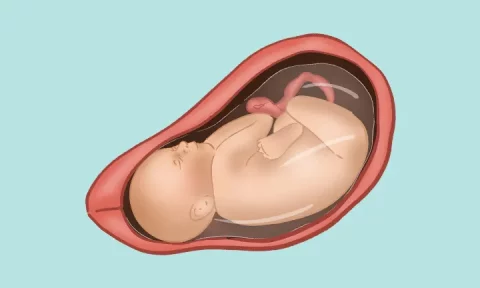

در طول دوران بارداری، توجه به رشد و تکامل جنین بسیار مهم است. از آزمایشهای ضروری مانند غربالگریها گرفته تا معاینات ماهانه، همه برای بررسی سلامت جنین انجام میشوند. همچنین، مطالعه درباره رشد و تربیت کودک و آمادگی برای یک تا ۱۲ ماهگی نوزاد، میتواند به والدین کمک کند تا برای این مرحله از زندگی آمادهتر باشند.